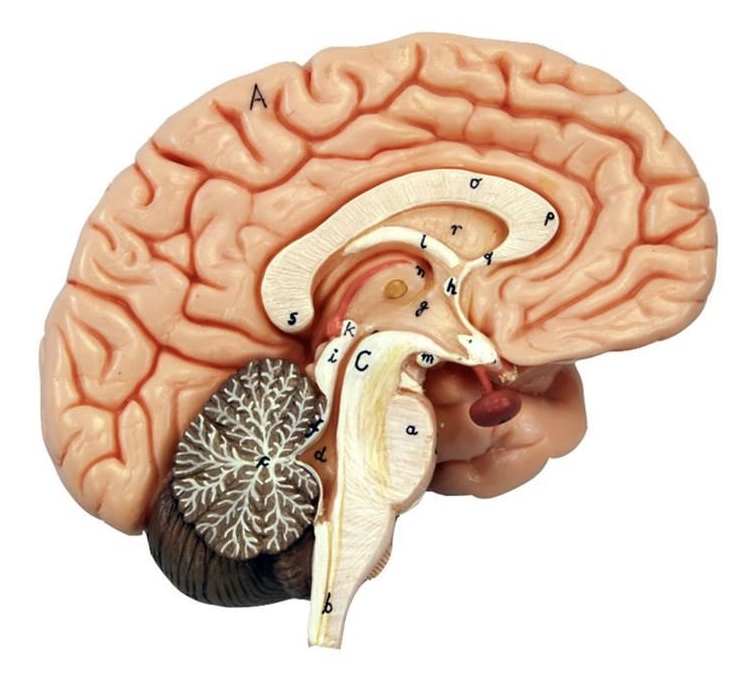

What is D?

lateral ventricle

Imagine thin membrane separating the 2 lateral ventricles

septum pellucidum

What is C?

3rd ventricle

What is B?

cerebral aqueduct

What is A?

4th ventricle

What is below A at the very end?

central canal (spinal cord)

What is C?

midbrain

tectum (corpora quadrigemina): superior colliculus

tectum (corpora quadrigemina): inferior colliculus

What is a?

pons

medulla oblongata

intermediate mass of thalamus

hypothalamus

What is the pink bulb?

pineal gland

corpus callosum

fornix

What is A?

cerebral cortex

cerebral tracts

cerebral hemispheres

longitudinal fissure

What are these ridges?

gyri

What are these shallow grooves?

sulci

Divides parietal from frontal lobe

central sulcus

precentral gyrus

postcentral gyrus